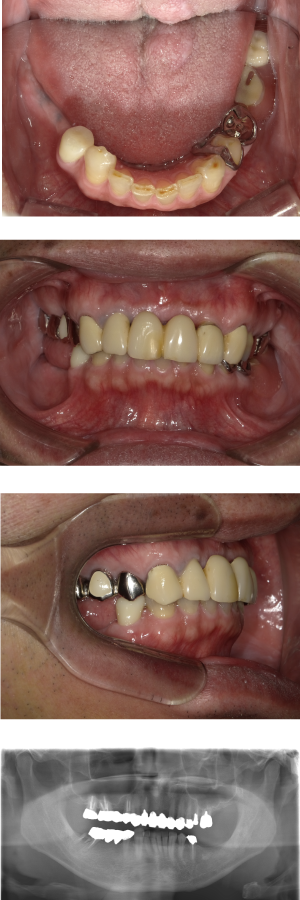

60代 女性 全顎 インプラント サイナスリフト等

| 年代・性別 | 60代・女性 |

| 主訴 | 上顎の入れ歯が割れた。リンゴやおかきを食べられるようになりたい。 |

| 部位 | 右上④3②・左上②3④5⑥のブリッジ |

| 治療期間 | 2年 |

| 費用 | ¥2,447,500(税込) |

| 副作用・リスク |